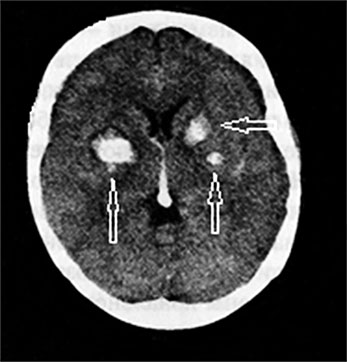

Есть очаги в головном мозге

Есть очаги в головном мозге 114 фото